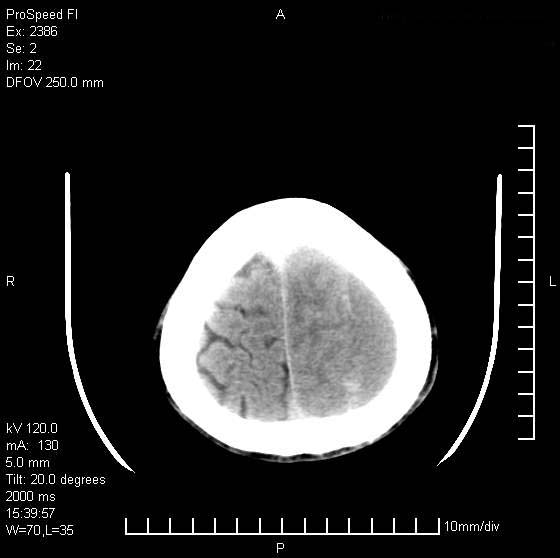

以下是引用天南地北在2007-9-19 18:43:00的发言:[br]典型慢性硬膜外血肿[br][br][本贴已被 天南地北 于 2007-9-19 18:44:11 修改过]

以下是引用曼一拍在2007-9-20 11:06:00的发言:[br]支持慢性硬膜下血肿.[br]慢性硬膜下积液:血肿有包膜,ct值稍高于脑脊液,增强可有染色。不典型者血肿可多呈梭形.是硬脑膜与蛛网膜之间的潜在腔隙内的血肿。[br]鉴别:[br]1\\硬膜外血肿:是颅脑外伤后脑膜或板障内血管破裂,血液在颅骨与硬膜之间积聚所致.通常是脑膜动脉破裂,也可因静脉窦破裂或颅骨的板障静脉出血,发生于外伤的着力部,常与颅骨骨折并存。脑膜动脉出血则急,若是板障静脉出血在则可有慢性。[br]2\\硬膜下积液:(硬膜下水瘤)[br]是由于蛛网膜破裂,脑脊液经蛛网膜破口进入硬膜下腔不能回流。或水肿阻塞而形成。[br]ct表现:颅骨内板下方新月形低密度区近似脑脊液密度;占位效应清,周围无脑水肿。[br]